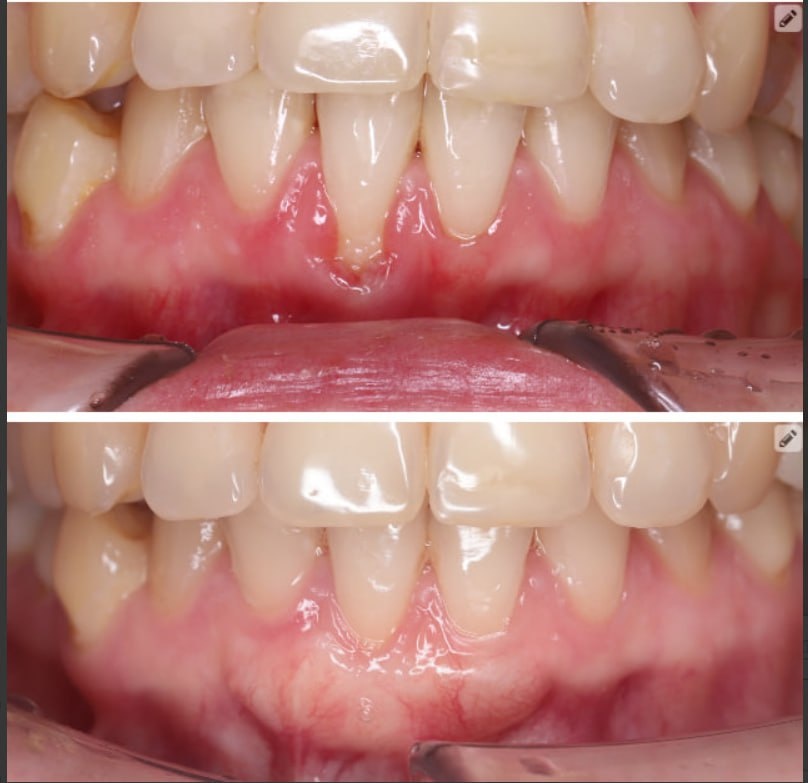

Десна краснеет и кровит при чистке - значит, я травмирую щёткой?

Чаще наоборот: кровь - это признак воспаления, а не «слишком старательная щётка».

На фото - мой пациент. На фоне оголения корня и воспаления ситуация постепенно прогрессировала, поэтому мы решили проблему хирургически - с помощью пластики десны.

Но важно понимать: если операция не проводится, домашняя гигиена должна быть практически идеальной. А при оголённом корне это сделать намного сложнее.